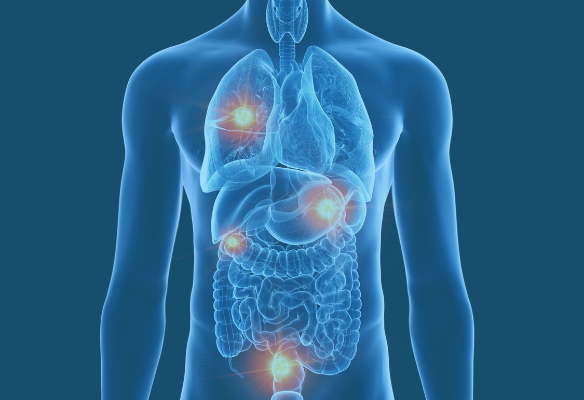

There’s a paradigm shift taking place: We’re moving from an organ-focused (type of cancer) approach to a gene-focused approach (cancer genomics). This shift is already having a profound effect on the way cancer is treated and allows doctors to provide more individualized options for patients (also known as precision medicine). NFCR has distinguished itself from other organizations by emphasizing long-term, transformative research and working to move people toward cancer genomics.

NFCR-funded researchers are all, in some way, using cancer genomics, but there are still certain cancer types that are most impacted by their projects. Specifics about those projects – as well as the cancer diagnoses – are outlined on the “Cancer Types” pages below.